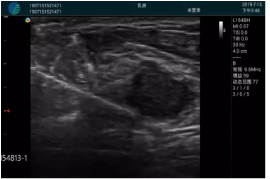

腺體內(nèi)部清晰顯示一低回聲塊影,形態(tài)不規(guī)則,邊界模糊,邊緣呈毛刺狀,內(nèi)部見砂礫樣鈣化